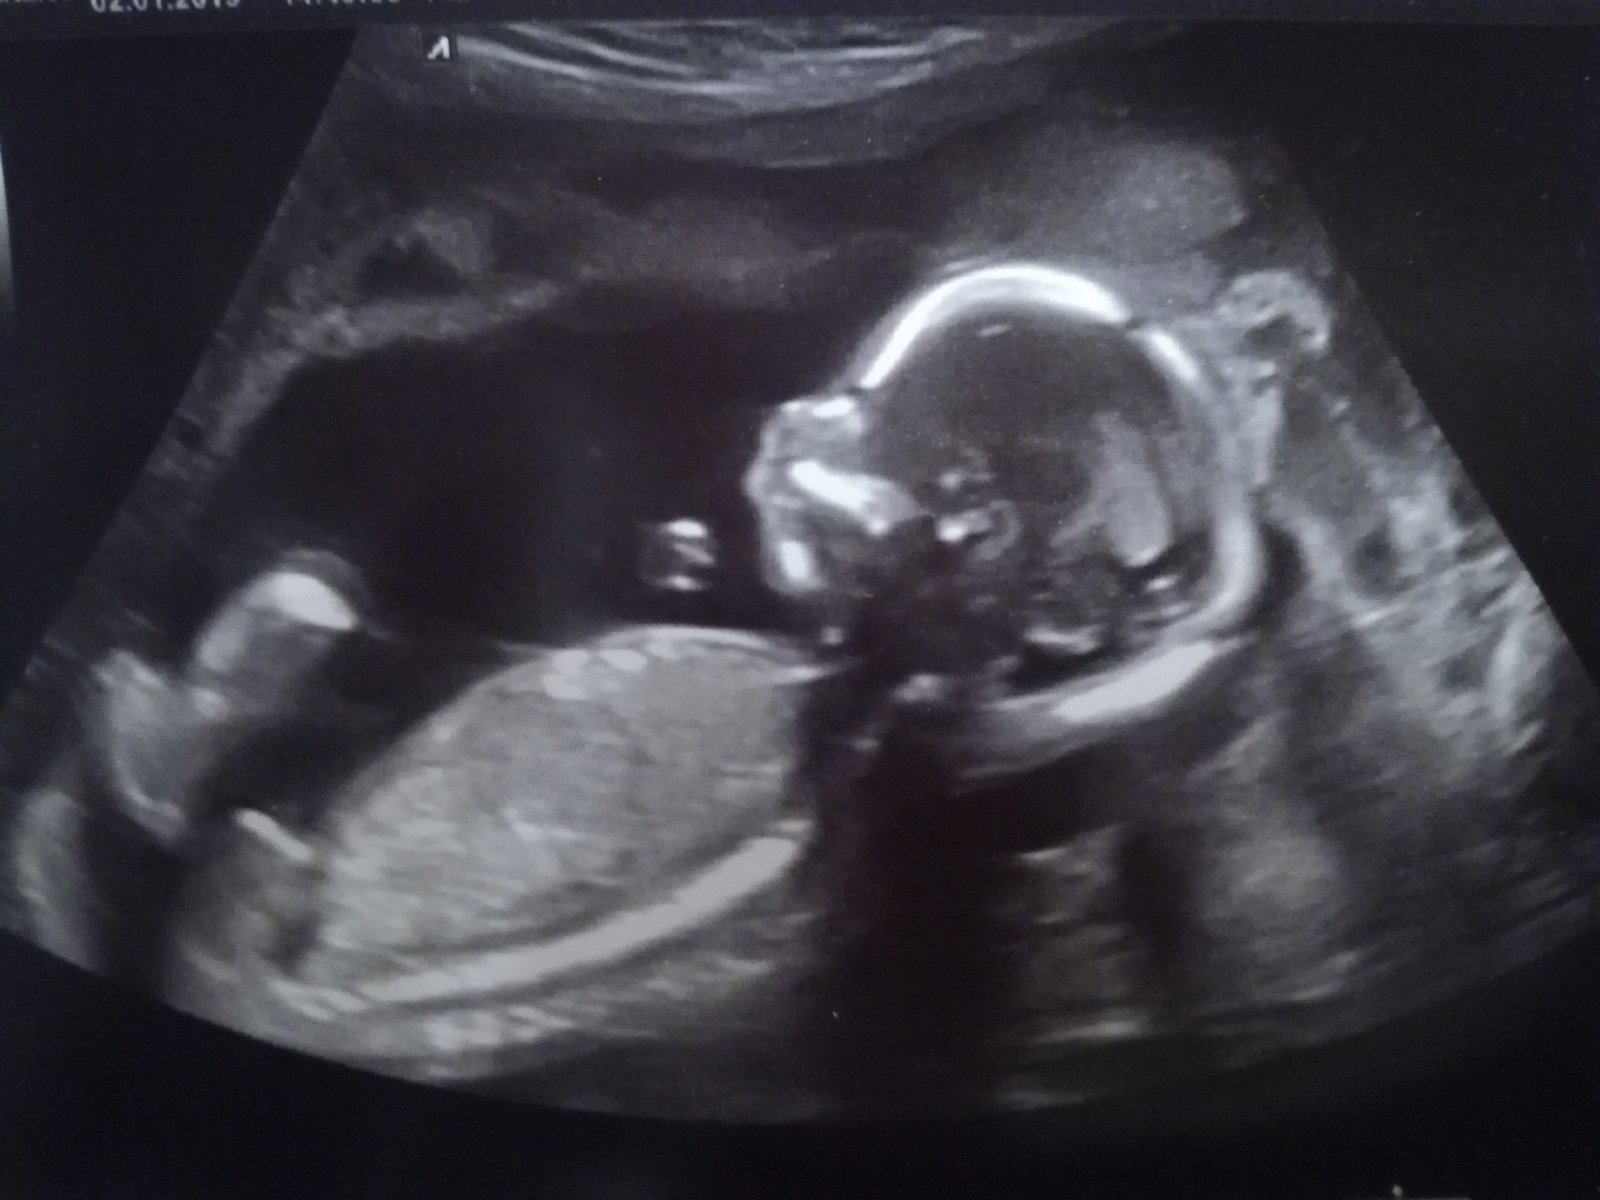

@janca209 jezis to je krasaaa, chce se mi brecet 😢😢😢😢😢

@janca209 To je krásná fotečka, jsou to neustálé nervy, hlavně že je vše v pořádku. Držím pěsti.

@lucik253 Ahojky, zrovna dneska jsem zažila pěkné nervy.. Odpoledne mi zvoní telefon, koukám na to a genetička, ta mi vždycky volá jen špatné zprávy. Řekla mi, že riziko pro Downa je nízké, v což jsem i doufala, když máme embryo prošlé genetikou, ale mám vyšší riziko pro rozštěpové vady. :( Měla jsem se okamžitě objednat na ultrazvuk, naštěstí centrum kam chodím na screening je v nemocnici, kde pracuju, tak jsem okamžitě se vším flákla a šla si to domluvit. Sestra už mě chtěla objednávat, ale šel okolo doktor a že má volno a vezme mě za 3/4 hodiny. Naštěstí se zdá být všechno v pořádku, spadl mi obrovský kámen ze srdce. Malej byl roztomilej, cucal si ručičku a dokonce se i v tu chvíli vyčůral. :lol: Je vidět, že nás měl na salámu. :mrgreen: Co ty? Jak se máš?